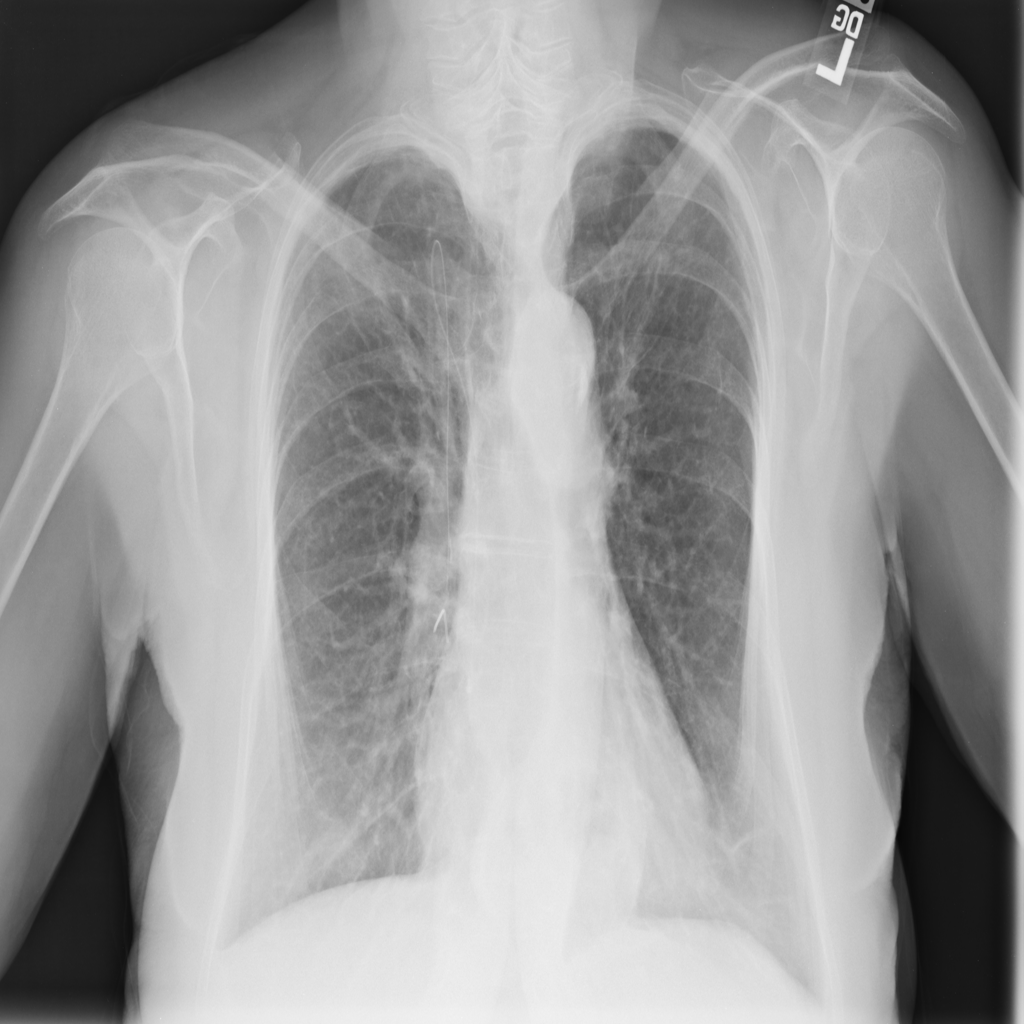

PAT-C048 · IMG-000Hernia

PAT-C048 · IMG-000

PA